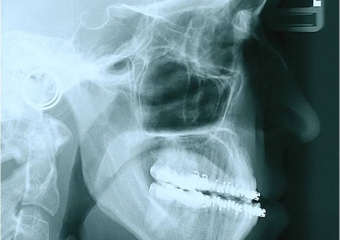

Telerradiografia inicial